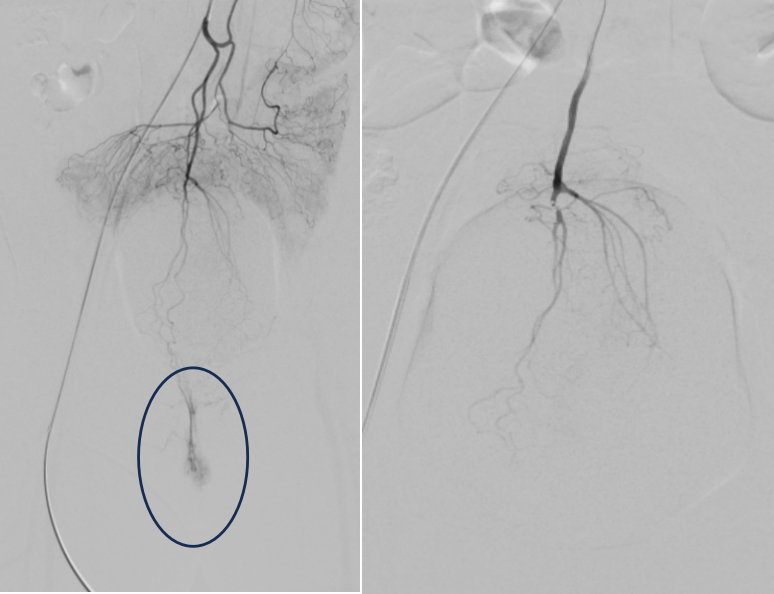

痔疮患者:手术前后对比痔疮血供消失